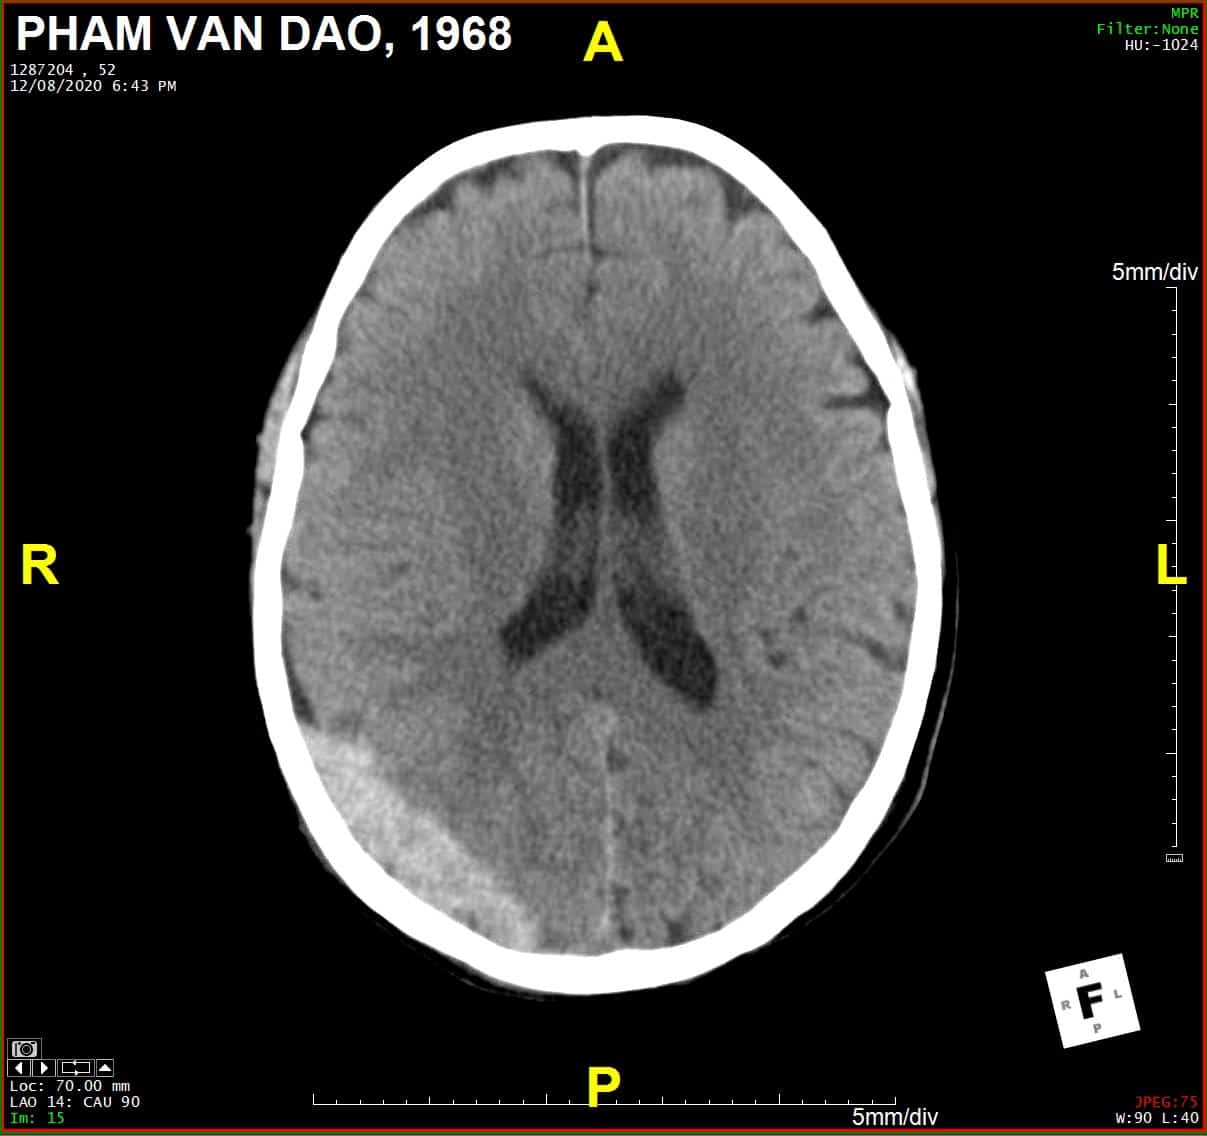

Chấn thương sọ

» Thông tin: Nam giới – 52 tuổi.

» Lâm sàng: Chấn thương sọ não.

# Tụ máu ngoài màng cứng vùng chẩm phải / Vỡ xương chẩm phải: đường vỡ thẳng (Linear fracture) không thấy rõ trên hướng cắt Axial => quan sát rõ trên hướng cắt Coronal và Sagittal.